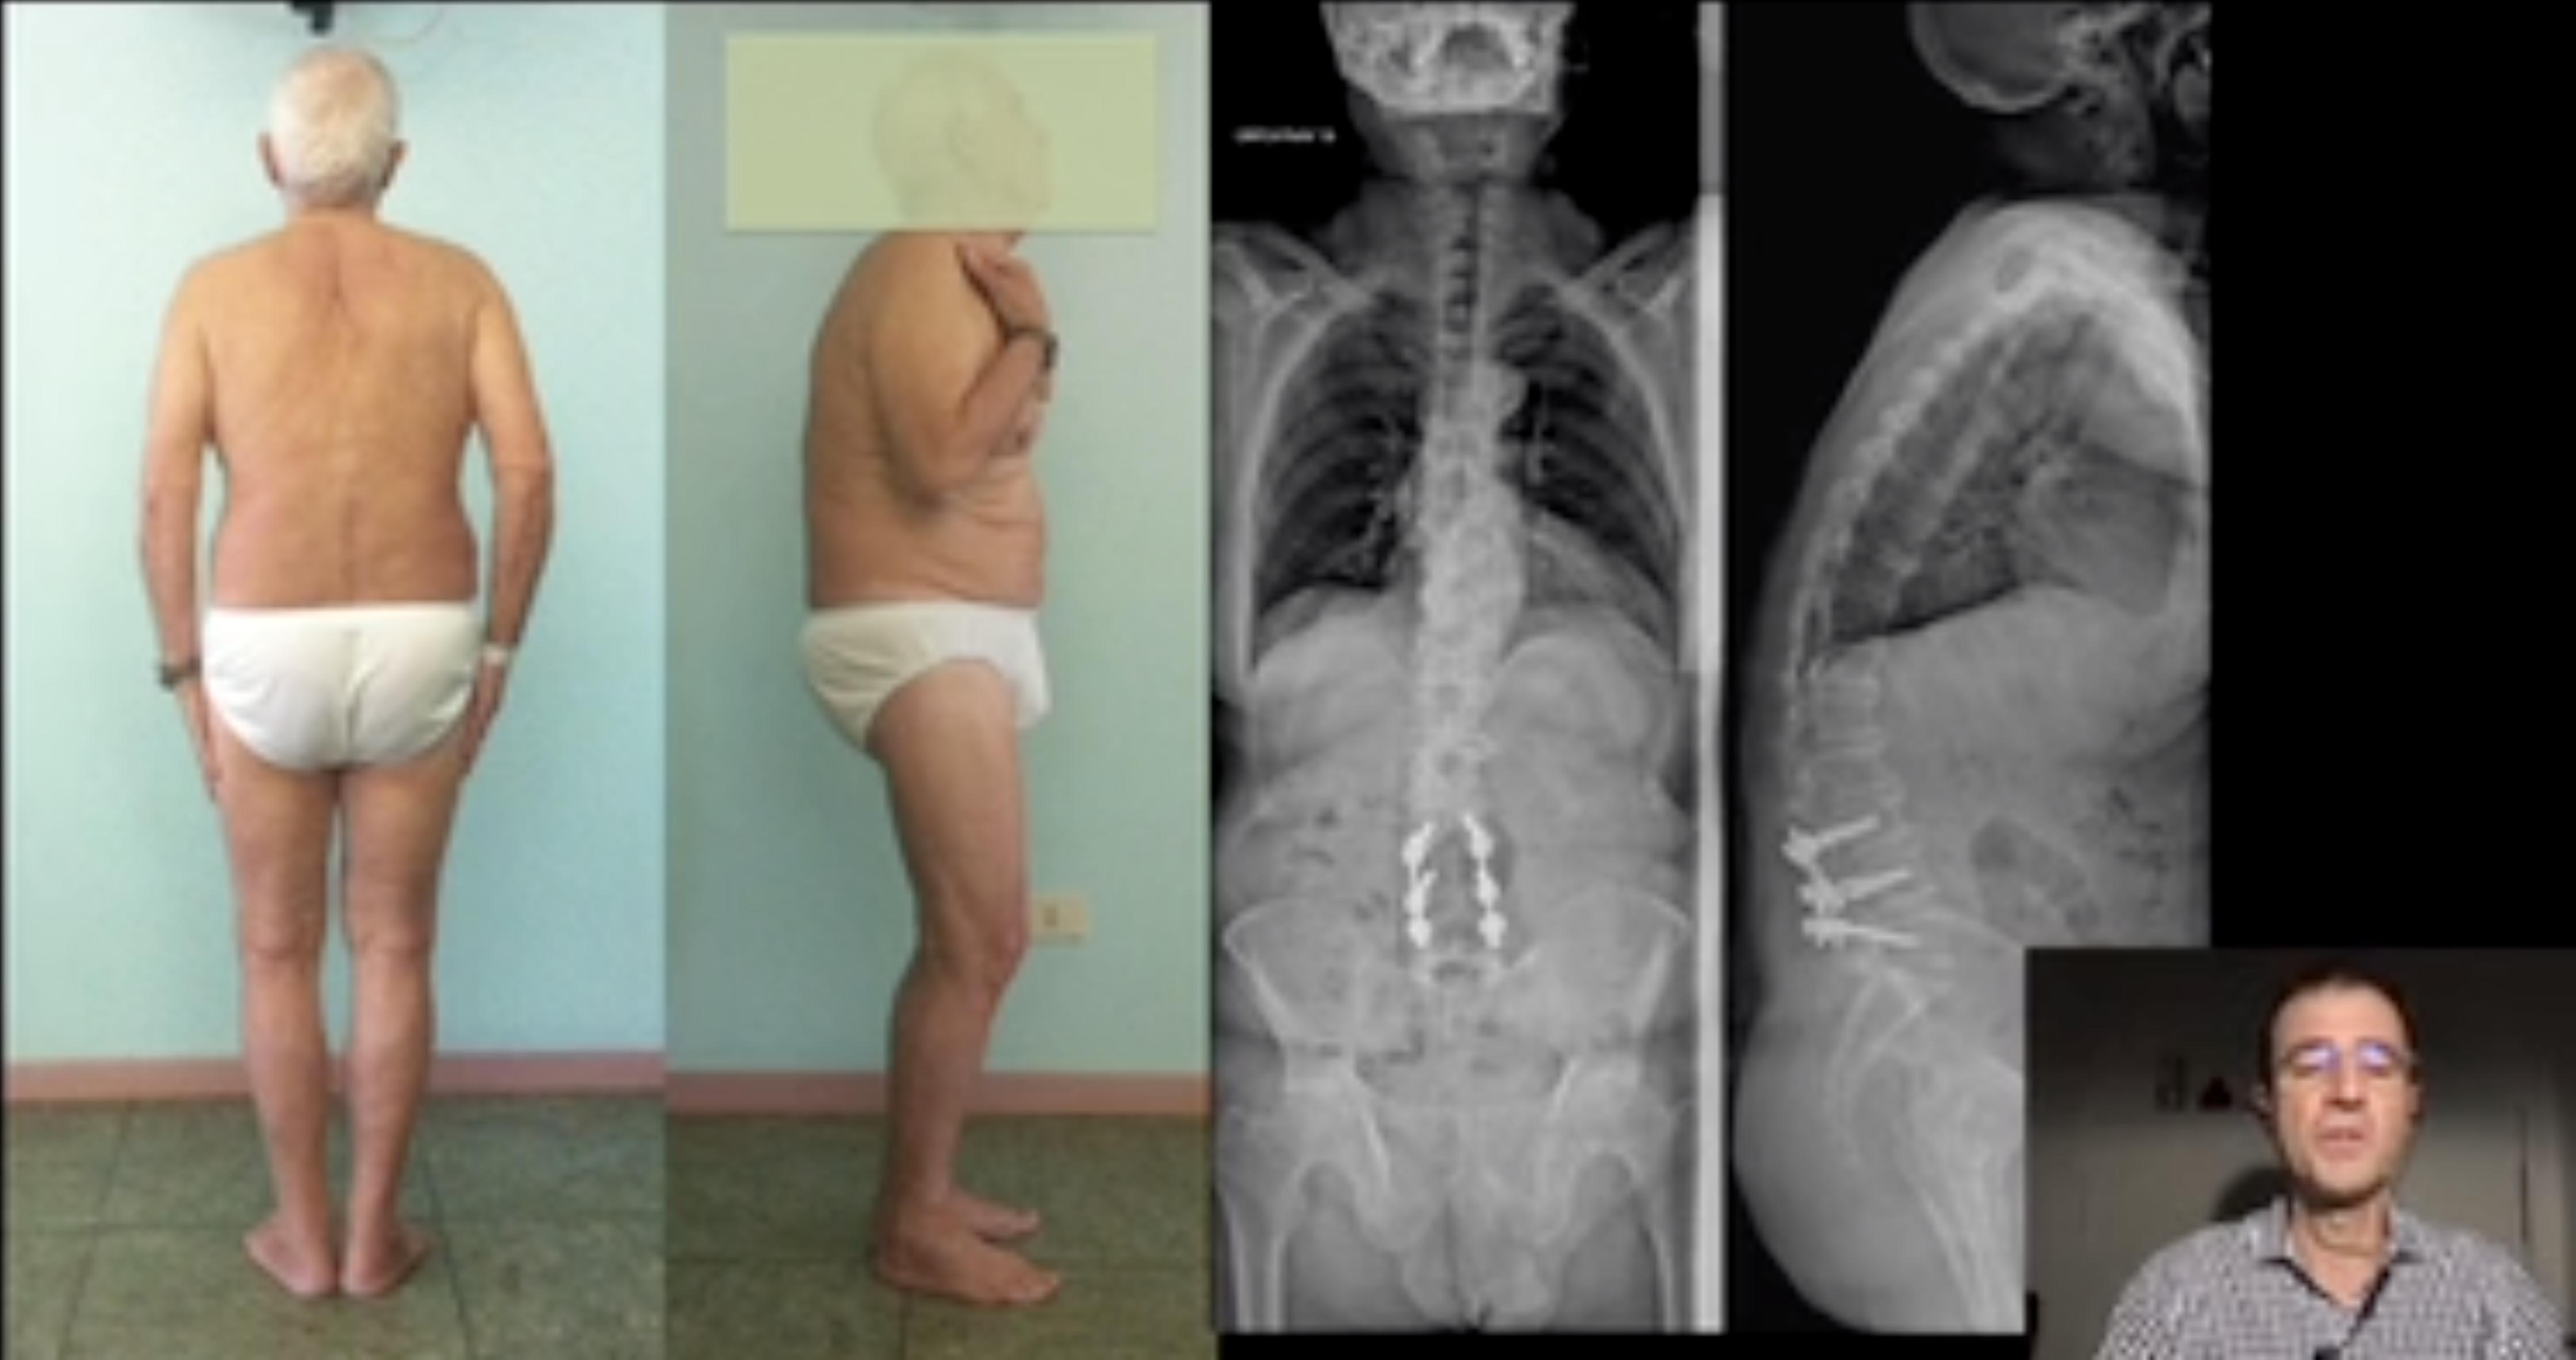

• A novel technique for sublaminar band-assisted closure of PSO

A novel technique for sublaminar band-assisted closure of PSO

Berjano Pedro MD, PhD

GSpine4

IRCCS Ospedale Galeazzi Sant'Ambrogio

Milan, Italy

Project 13-026

This video shows how to apply the principles of surgical planning in an elderly patient with sagittal imbalance, how to perform technicall...